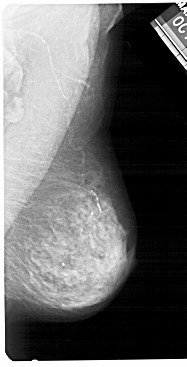

A_1393_1.RIGHT_MLO

RIGHT_MLO LINES 5491 PIXELS_PER_LINE 2791 BITS_PER_PIXEL 12 RESOLUTION 43.5 NON_OVERLAY